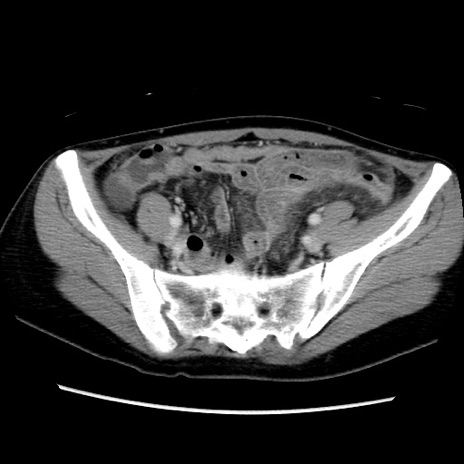

症例39(横断像)

【症例】40歳代女性

【主訴】上下腹部痛

【現病歴】2日目から下腹部痛あり。夜間は痛みで眠れなかった。昨日より上腹部痛と下痢が出現。臥位で痛みは軽快したため、休んでいた。本日になって臥位でも立位でも痛みが強くなってきたため救急要請。

【既往歴】子宮内膜症

【身体所見】部:平坦・軟、左上下腹部に圧痛あり、反跳痛あり。

【データ】WBC 21800、CRP 26.78